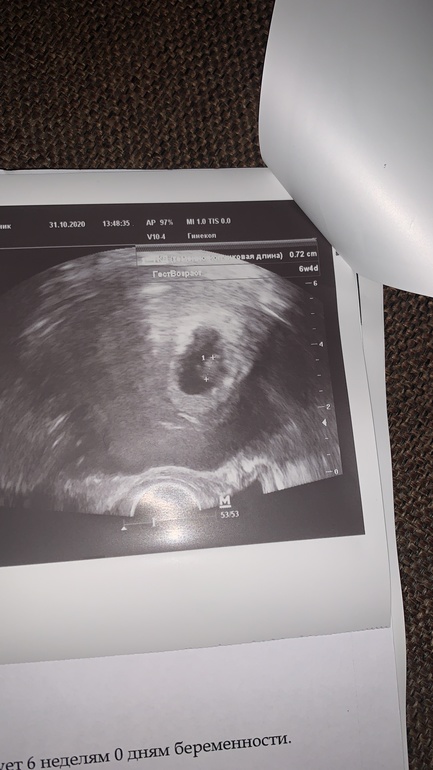

Оль, я уже не верю ничему. Вот смотри моё узи в 6.5 это одно узи, только разные ракурсы.

У меня 4 сына 🥰😅тоже разные способы пробовали, но результат - сыновья. трубы зашила после 4 беременности. Все КС 🤦♀️ Но вот прошло 8 лет и мы решили попробовать на последок ещё раз! Сделали ЭКО+ПГД получился всего один эмбриончик. Результат ПГД - образец не интерпретирован 😅 все равно подсадили, растём))) на фото 7 недель

Вы молодцы рискнули. По Рамзи у вас мальчик, если вагинальный датчик был🙈.

Датчик вагинальный, врач сказал прикрепление по передней стенке слева, я тут пересмотрела фото, так и не поняла как определяете)))